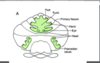

flocculonodular lobe

flocculus is lateral part of flocculonodular lobe

tf flocculonodular lobe is post to post lobe

ant to it

posterior lateral fissure

sep flocculonodular lobe and posterior lobe

Lateral Hemisphere

forms the bulk of the cerebellum

Paravermis:

Paravermis: R and L zones adjacent to the vermis

most medial of deep cerebellar nuclei (DCN)

receives projections from vermis

Fastigial nucleus •

lateral to fastigial n.

receives projections from paravermis

Globose nucleus

Emboliform nucleus

lateral to globose n

receives projections from paravermis

Dentate nucleus

• most lateral •

receives projections from lateral hemisphere